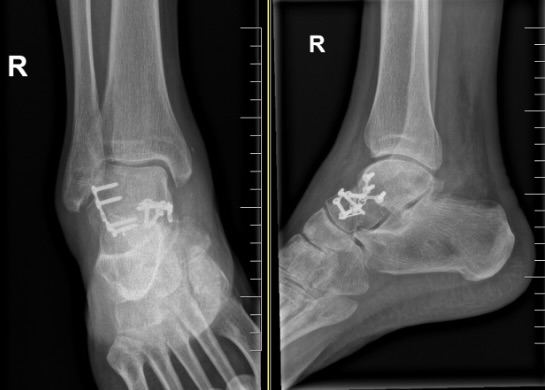

Fracturas de Calcáneo

Las fracturas de calcáneo (hueso del talón) son lesiones frecuentes por caídas de una altura o accidentes de tráfico.

Cursa con gran inflamación y dolor que imposibilita el apoyo del pie y caminar.

La reconstrucción de estas fracturas es compleja y no exenta de complicaciones, por lo que es recomendable sean tratadas por cirujanos expertos. En nuestra Unidad tenemos amplia experiencia en el tratamiento de estas lesiones, tanto en la reconstrucción de las lesiones agudas como en la de las secuelas

Las radiografías y sobretodo el TAC ayudan a clarificar el tipo de fractura, el desplazamiento de los fragmentos óseos y el tratamiento a seguir.

El tratamiento intentará restablecer la anatomía, siendo para ello necesaria la intervención quirúrgica y la reconstrucción con placas específicas y tornillos.